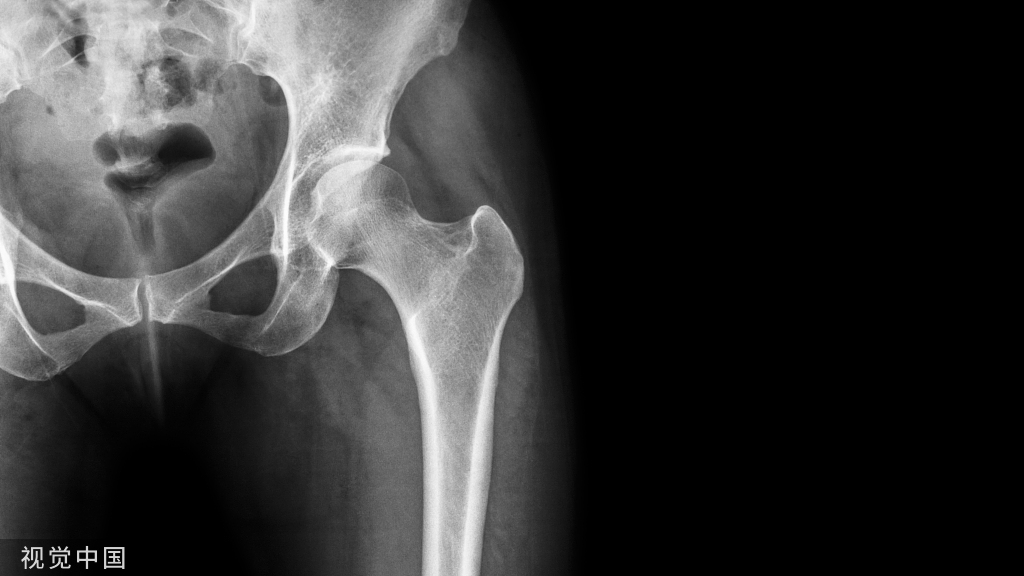

03

腰4骨质疏松性骨折